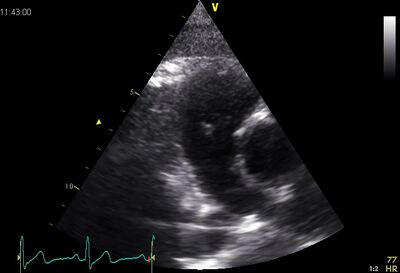

| Plax by tilted (Plax PV) | PSax Ao |

|---|---|

|

|